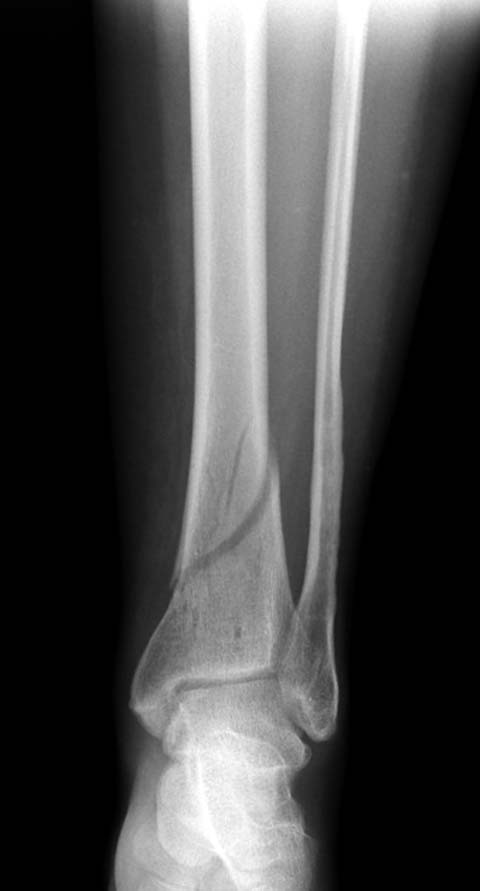

Первый случай, где перелом в результате падения с  небольшой высоты, где

мортиз рентген снимок показал отстутствие укорочения наружной

лодыжки и КТ срезы подсказали направления атаки. После такой фиксации

нет надобности в гипсовой повязке, брейс и через две недели движения в

суставе без нагрузки.